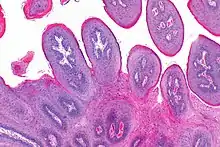

![]() | Squamous papilloma | Micrograph showing squamous cell papilloma of the tongue. | Category: Histopathology of squamous cell carcinoma | Squamous papilloma |